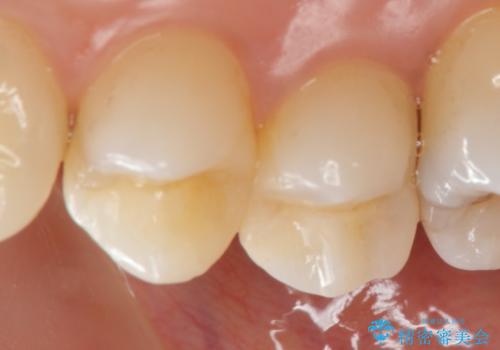

マイクロスコープで神経を保存できるよう丁寧に虫歯を除去したのちセラミックインレーにて高精度な修復を行っていきます。

- 14万円(emaxインレー×2)費用は治療当時の料金となります

セラミック治療は精密な歯牙形態の形成、シリコン印象により高い精度と審美性・予知性が達成されます。